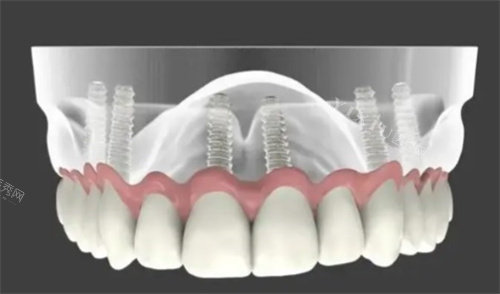

种植牙

采用ALL-ON-4/6全口种植技术,结合3D导板精细定位,实现小创口、快速、稳定的种植结果,尤其适合半口或全口缺牙患者。